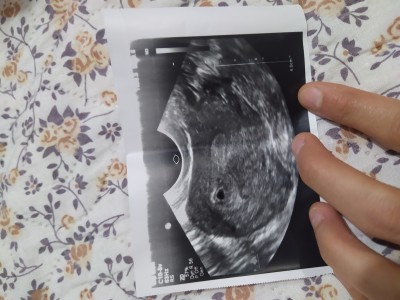

İki tane kese mi var anlayan var mı

Kızlar son adet tarihime göre 5+4 günlüğüm 5 gün önce doktorum vajinal ultrasonla baktığında keseyi gördü ben pek anlamıyorum da gerçekten bilen biri yorumlayabilir mi kese kaç santim bide dediğim gibi pek anlamıyorum iki kese mi var ben mi yanlış görüyorum biri sağda biri solda bakar mısınız

Yalnızca solda bir kese var. Kesenin kaç mm olduğu da ultrason kağıdında yazar. Yazılı kısımları çekmemişsiniz ki kaç mm olduğu sizlik bir durum değil. Bir sorun olsaydı doktor zaten söylerdi size. Söylememişse bir sorun yok demektir.

Sağ tarafta da bı tane var sandım orasida karanlık ya bide yeni bı foto ekledim haftama göre nasıl kese merak ettim sadece

İki kese görünmüyor bence

Ben ikizlere hamileyim benim ultrason fotoğraflarından çok farklı geldi bana

1 tane kese var cnm

Sağdaki kısım rahimde değil. Rahim, orta kısımda armut şeklinde bir yapı var orası.

Yok canım 1 kese var

Kesen 1 cm canim daha bebek de tek ikiz olsa doktorun söylerdi